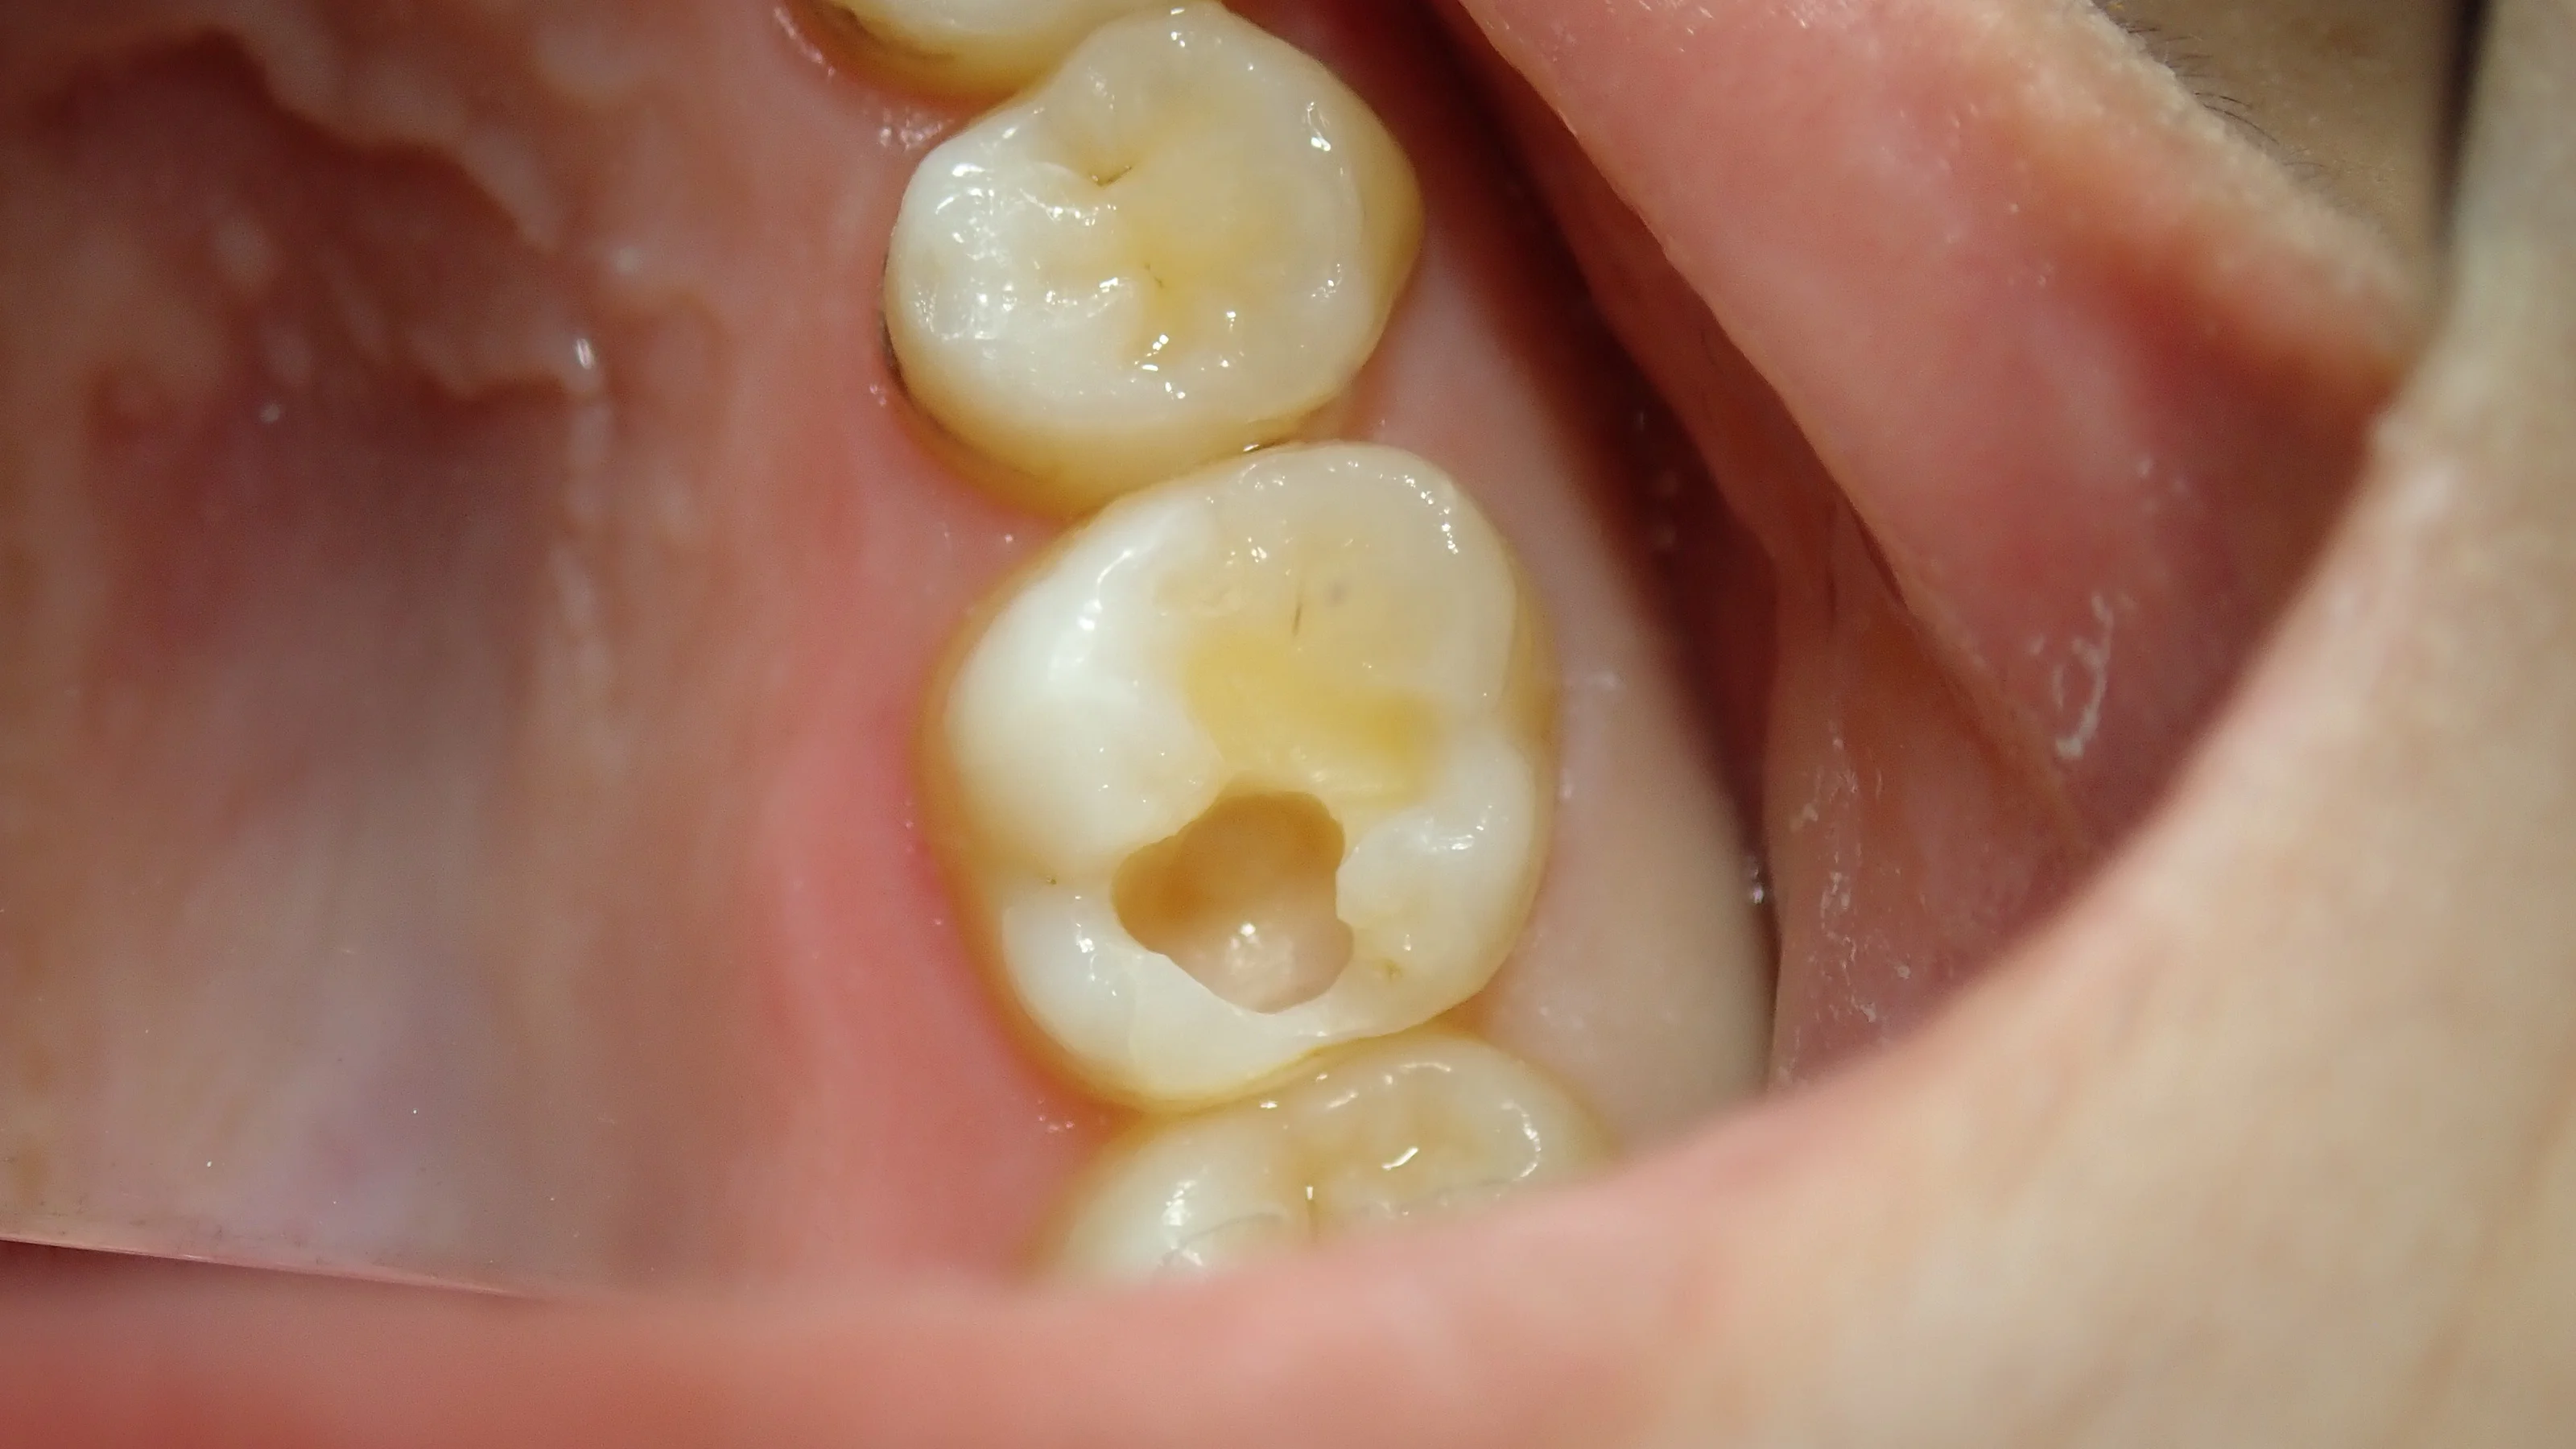

恒例の術前術後がこちらです。

術後、染みも無くなり、噛んだ時の違和感も消えたそうで、ホッとしました。